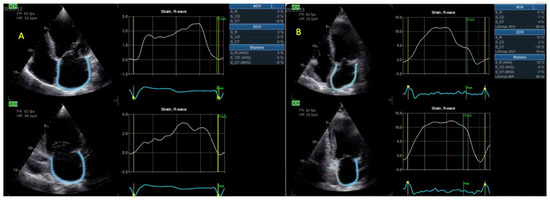

| LVGLS (%) | 7.9 ± 3 | 6.2 ± 2 | 0.008 |

| BP LASr (%) | 12.3 ± 7 | 6.9 ± 3 | <0.001 |

| RVFWLS (%) | 17.2 ± 7 | 13.2 ± 5 | 0.004 |

| RASr (%) | 22 ± 12 | 9 ± 6 | <0.001 |